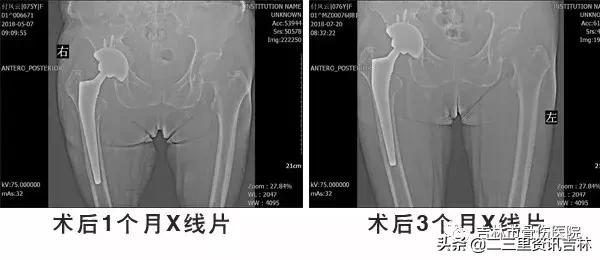

患者入院后给予常规检查,经三级医师查房,临床诊断确诊,经过科内及院内医生会诊,查无明显手术禁忌症后在腰硬+全麻下行“右侧全髋关节置换术后假体松动关节翻修术”,术中我们沿原手术切口瘢痕切开皮肤、皮下及深筋膜,切开关节囊,活动髋臼杯见髋臼杯假体活动,依次取出内衬及髋臼杯,见髋臼内陷,髋臼壁薄弱,原有的髋臼结构及承重结构已破坏、消失,我们取同种异体骨材料用咬骨钳处理成大小不一的若干个骨块,万古霉均匀素涂后倒入髋臼处,*压打**植骨,抹平后用髋臼锉处理髋臼,脉冲冲洗,外用万古霉素,然后根据术前测量的髋臼大小,置入型号为Φ64/32mm3D打印金属髋臼,活动髋臼较稳定,并以3枚螺钉固定,放入内衬,活动内衬较稳定。活动原有股骨柄假体见略有微动,用打拔器取出原有股骨柄,髓腔挫扩髓,植入型号为8#的股骨柄,安装32mm球头。复位,试行关节外展、内收、前屈、后伸、旋转各方向活动,见关节稳定性良好,纵向牵拉,活动度约1厘米。对比健侧,双下肢基本等长。逐层缝合,术终。术后给予抗感染、消肿、抗凝关节功能松动练习等对症治疗,术后患者自诉疼痛明显减轻,现患者及其家属对当前治疗表示满意。

X线片示:右侧人工髋关节置换术后影像,髋臼内陷,髋臼壁薄弱,原有的髋臼结构及承重结构已破坏、消失,股骨柄下沉,余未见明显异常。